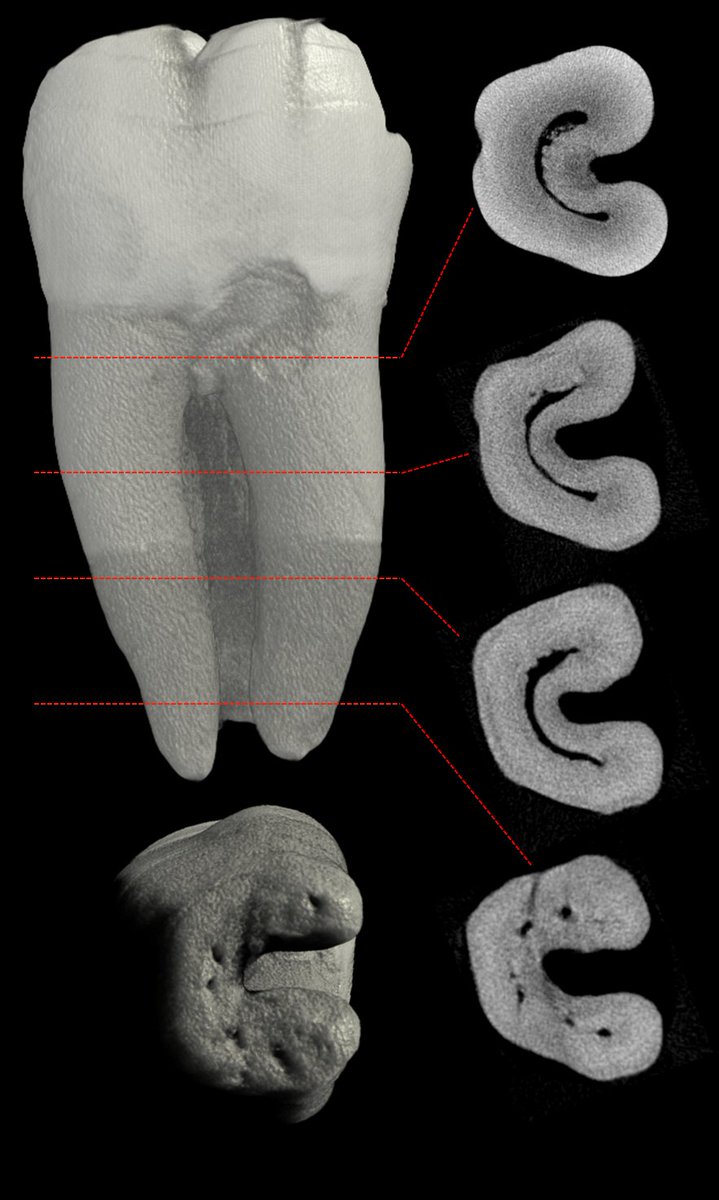

A C-shaped canal system can be observed in many variations

in root and canal morphology. It can vary along the root depth so the appearances of

the orifices are not necessarily good predictors of the actual canal anatomy.

🔴Fan et al in 2004 modified Melton’s method of classification into the following categories 🔴

1️⃣Category I (C1):

The shape is an uninterrupted “C” with no separation or division.

2️⃣ Category II (C2):

The canal shape resembles a semicolon resulting from a discontinuity in the “C” outline, but either angle α or β should be no less than 60°.

3️⃣Category III (C3):

Two or three separate canals and both angles, α and β, are less

than 60°.

4️⃣Category IV (C4):

Only one canal, which is round or oval in cross section